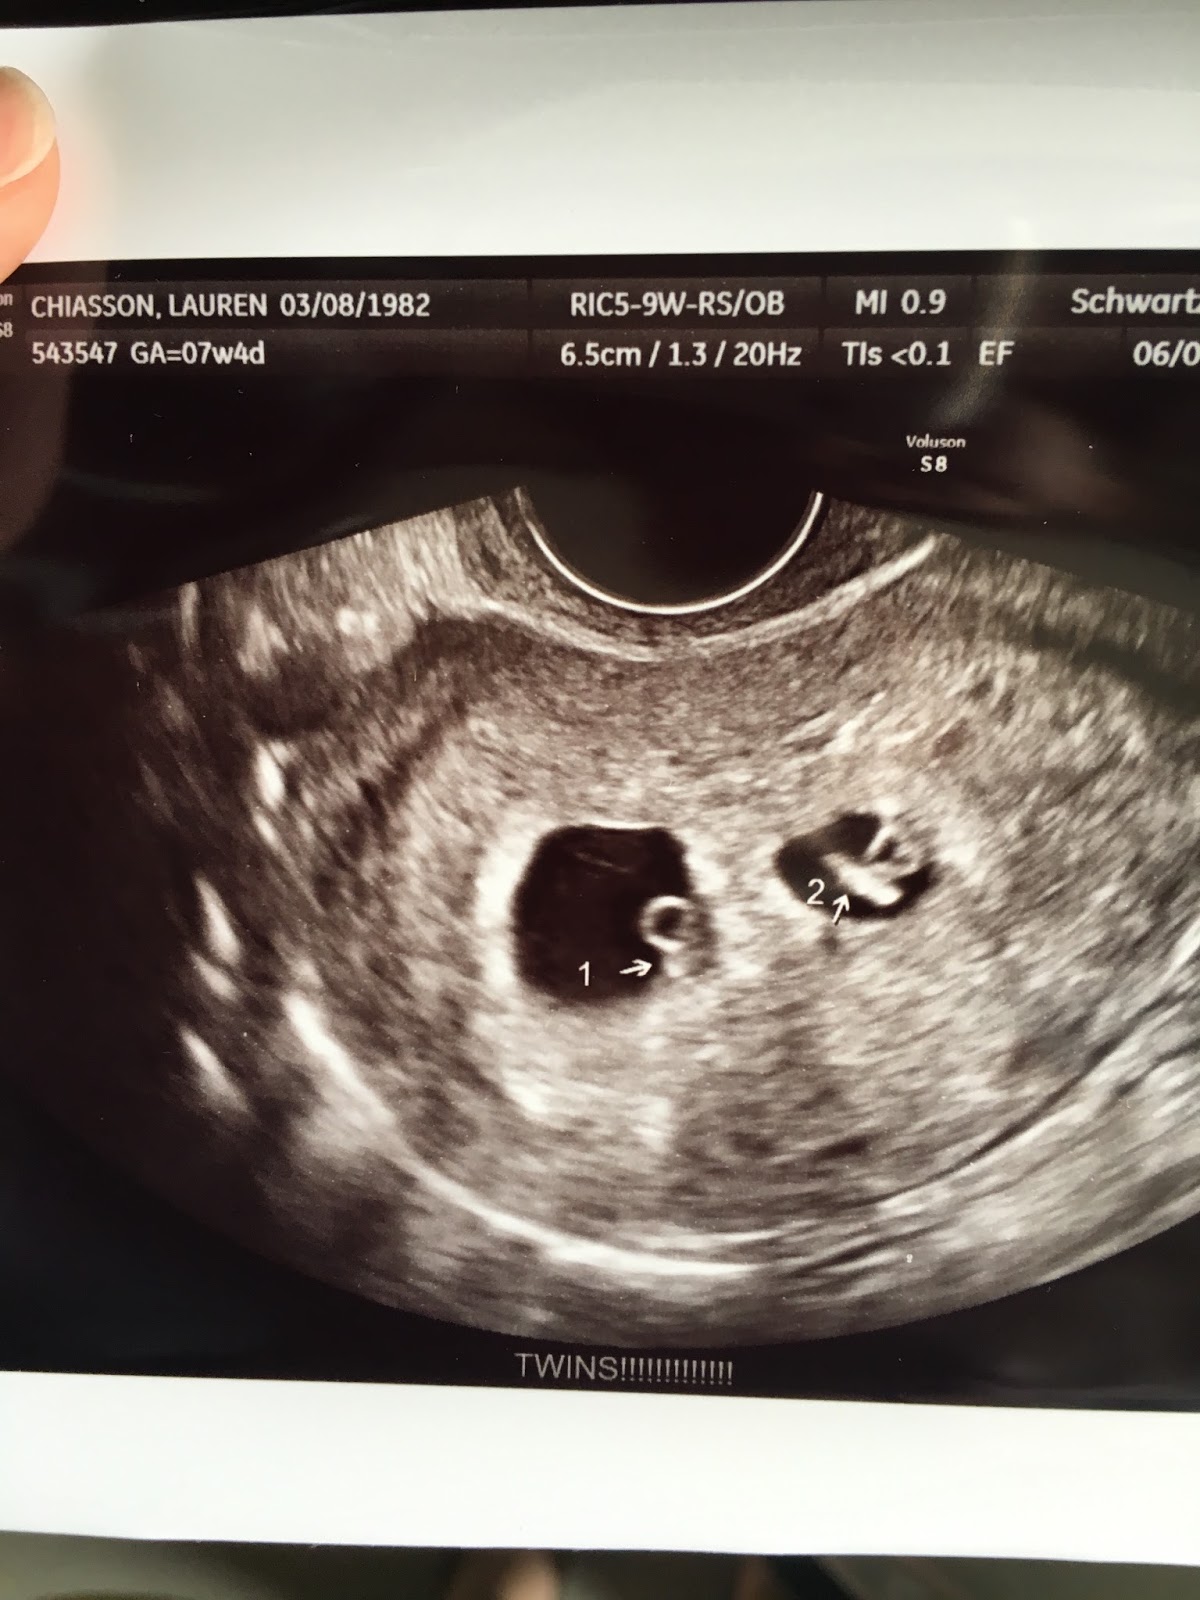

What a day!!! Mommy went to her first doctor's appointment today to check on your little brother/little sister. Dr. Chapman called this morning and rescheduled my ultrasound for this morning, so Daddy was unable to make it. (He was in New Orleans for work.) So, Mommy brought you with her to her doctor's appointment by herself. When the ultrasound technician rubbed her wand over Mommy's tummy, I immediately saw TWO babies!! I was shocked!!! I yelled out, "That's two babies!! That's two!!" I was shaking and wanted Daddy to be there so badly. After meeting with my doctor and doing all of my lab work, I drove home. I couldn't stop shaking and crying. (You were so good during my appointment, by the way!) I called Daddy and asked him to come home as soon as he could. When he got home, I showed him the ultrasound picture. He dropped it, along with his jaw, and was speechless. You are going to be the big sister to TWO babies!!